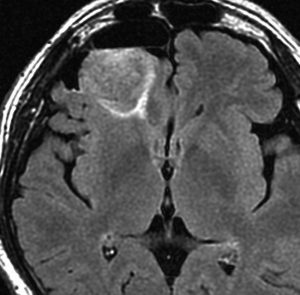

テモゾロマイド単独化学療法の例

2010年無症状の時の画像です。こんなのを手術で摘出したら認知機能が落ちて人格が変わります。だから経過観察しました。

2015年のテモゾロマイドを開始する前の画像です。2014年にちょびっと生検術をして1p/19q欠失,IDH変異はわかっていました。2015年に全般発作を起こしたので治療を開始しました。テモゾロマイドを 2年 24コース続けました。乏突起膠腫は大きくなる時,てんかんを生じることが多いです。

2020年の画像です。腫瘍はかなり小さくなって再燃(再発)していません。てんかんも抑制されて発作はありません。無症状です。

この例は,手術も放射線治療もしないで,乏突起膠腫が10年以上,制御できることを示しています。また,テモゾロマイド治療でてんかん発作が少なくなることも有名な事実です。

でも,現実はこんなに甘くない?  2025年時点で,治癒を目指すなら低線量放射線治療を加えるべきと考えられています。